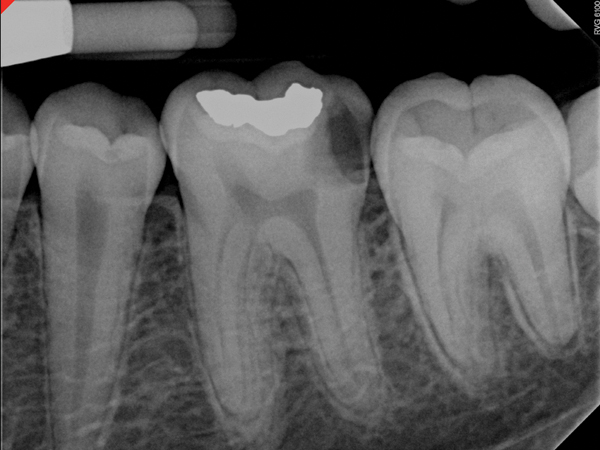

Figure 6. Preoperative radiograph of carious exposure on tooth No. 19. Courtesy of Dr. Mohammed A. Alharbi.

Figure 6

Figure 9. Immediate postoperative radiograph. Courtesy of Dr. Mohammed A. Alharbi.

Figure 9

Figure 10. Radiograph taken at 6-month follow-up visit. Courtesy of Dr. Mohammed A. Alharbi.

Figure 10